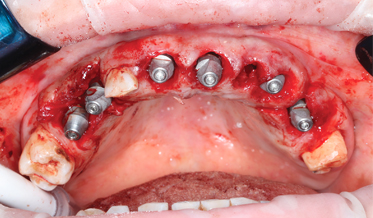

Step By Step